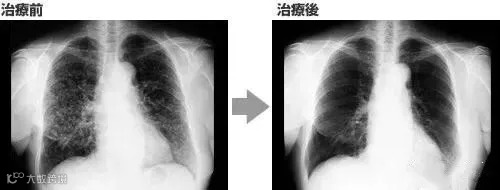

案例3:一名广泛期小细胞肺癌患者,在进行4个疗程化疗和4次高度活化NK细胞临床干预后,患者第一次进行治疗后的CT复查,结果显示,肿瘤缩小到了原来的1/8。而且距发病第六年的CT复查中,仍旧没有发现任何异常及复发的迹象。